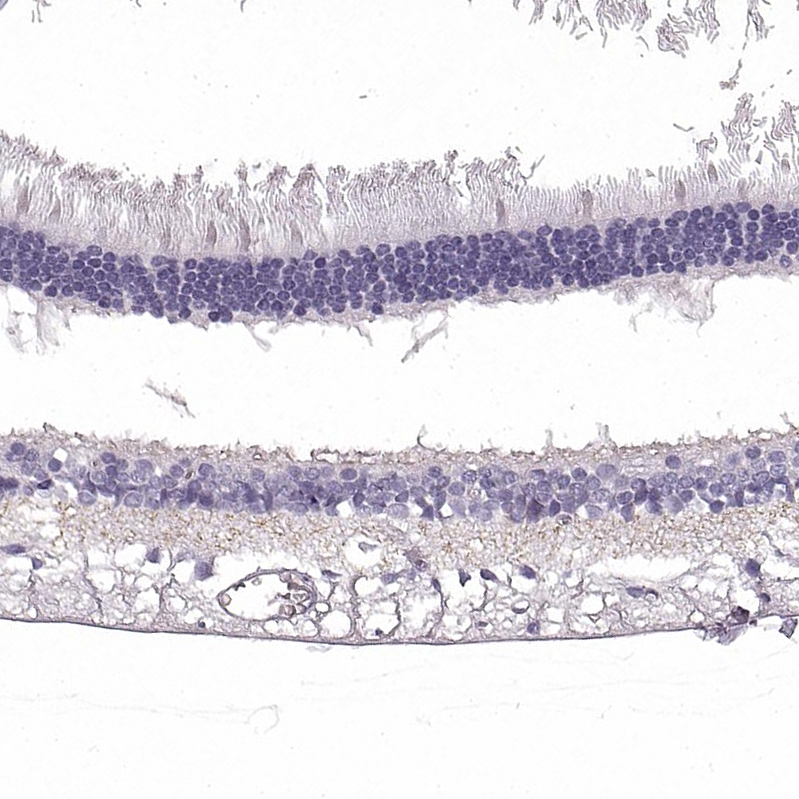

Immunohistochemical staining of human eye, retina shows weak granular cytoplasmic positivity in nerve fibers in plexiform layers.